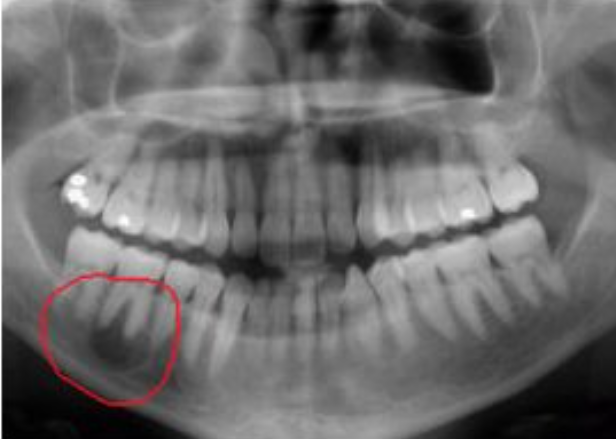

• Киста - уже финальный этап. Это оформленное образование, окружённое капсулой, имеющее тенденцию к росту. Отличить одно от другого точно может только врач по результатам рентгена и, при необходимости, КТ.

Чтобы не попадать в подобные ситуации - хотя бы раз в год делайте контрольный рентген и если, вдруг, почувствовали дискомфорт - не ждите, что "все пройдет само по себе".